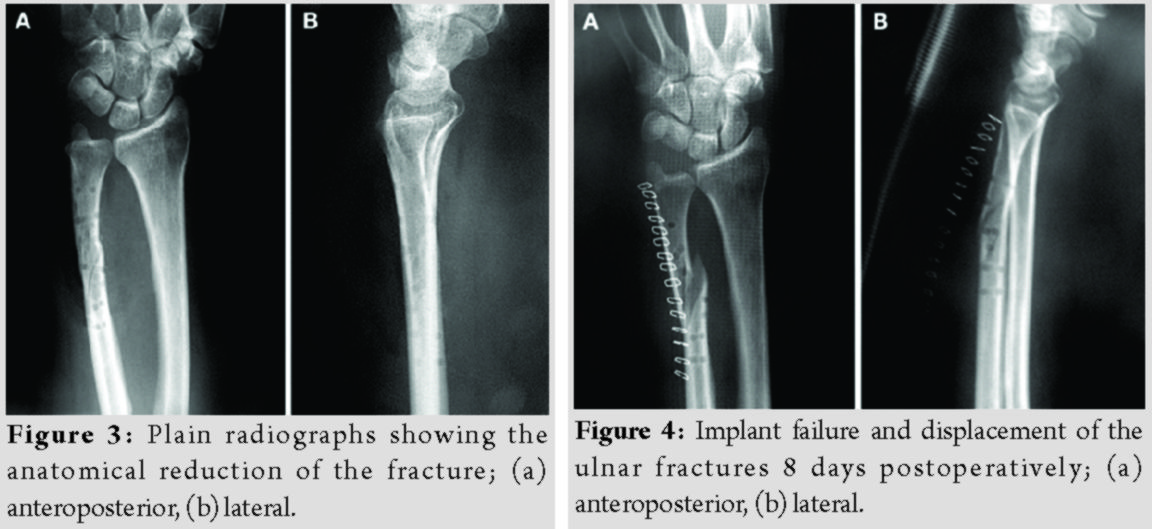

Radiographs were obtained immediately postoperatively (Fig. 3). Sugar-tong splint immobilization was maintained for 6 weeks to avoid rotation of the forearm and the patients were advised to initiate hand rehabilitation exercises immediately postoperatively; elbow exercises were scheduled after removal of the aforementioned splint.

The patients’ demographics and comorbidities are shown in Table 1. All three patients reported pain and unexpected swelling few days after the operation and the implants’ failure was confirmed radiologically (Fig. 4).

Reoperation using metallic implants was proposed as a definitive treatment for all patients. However, two of them denied it and were further treated with a plaster of Paris cast. The other patient, a 55 years old woman, underwent a revision fixation using a 3.5 metallic plate and screws.

The fragmented absorbable plate was removed (Fig. 5), and a 3.5 mm metallic plate and screws were used for refixation. Subsequently, all fractures healed uneventfully (Fig. 6). The patients’ grip strength and DASH score at 9 months are presented in Table 2.